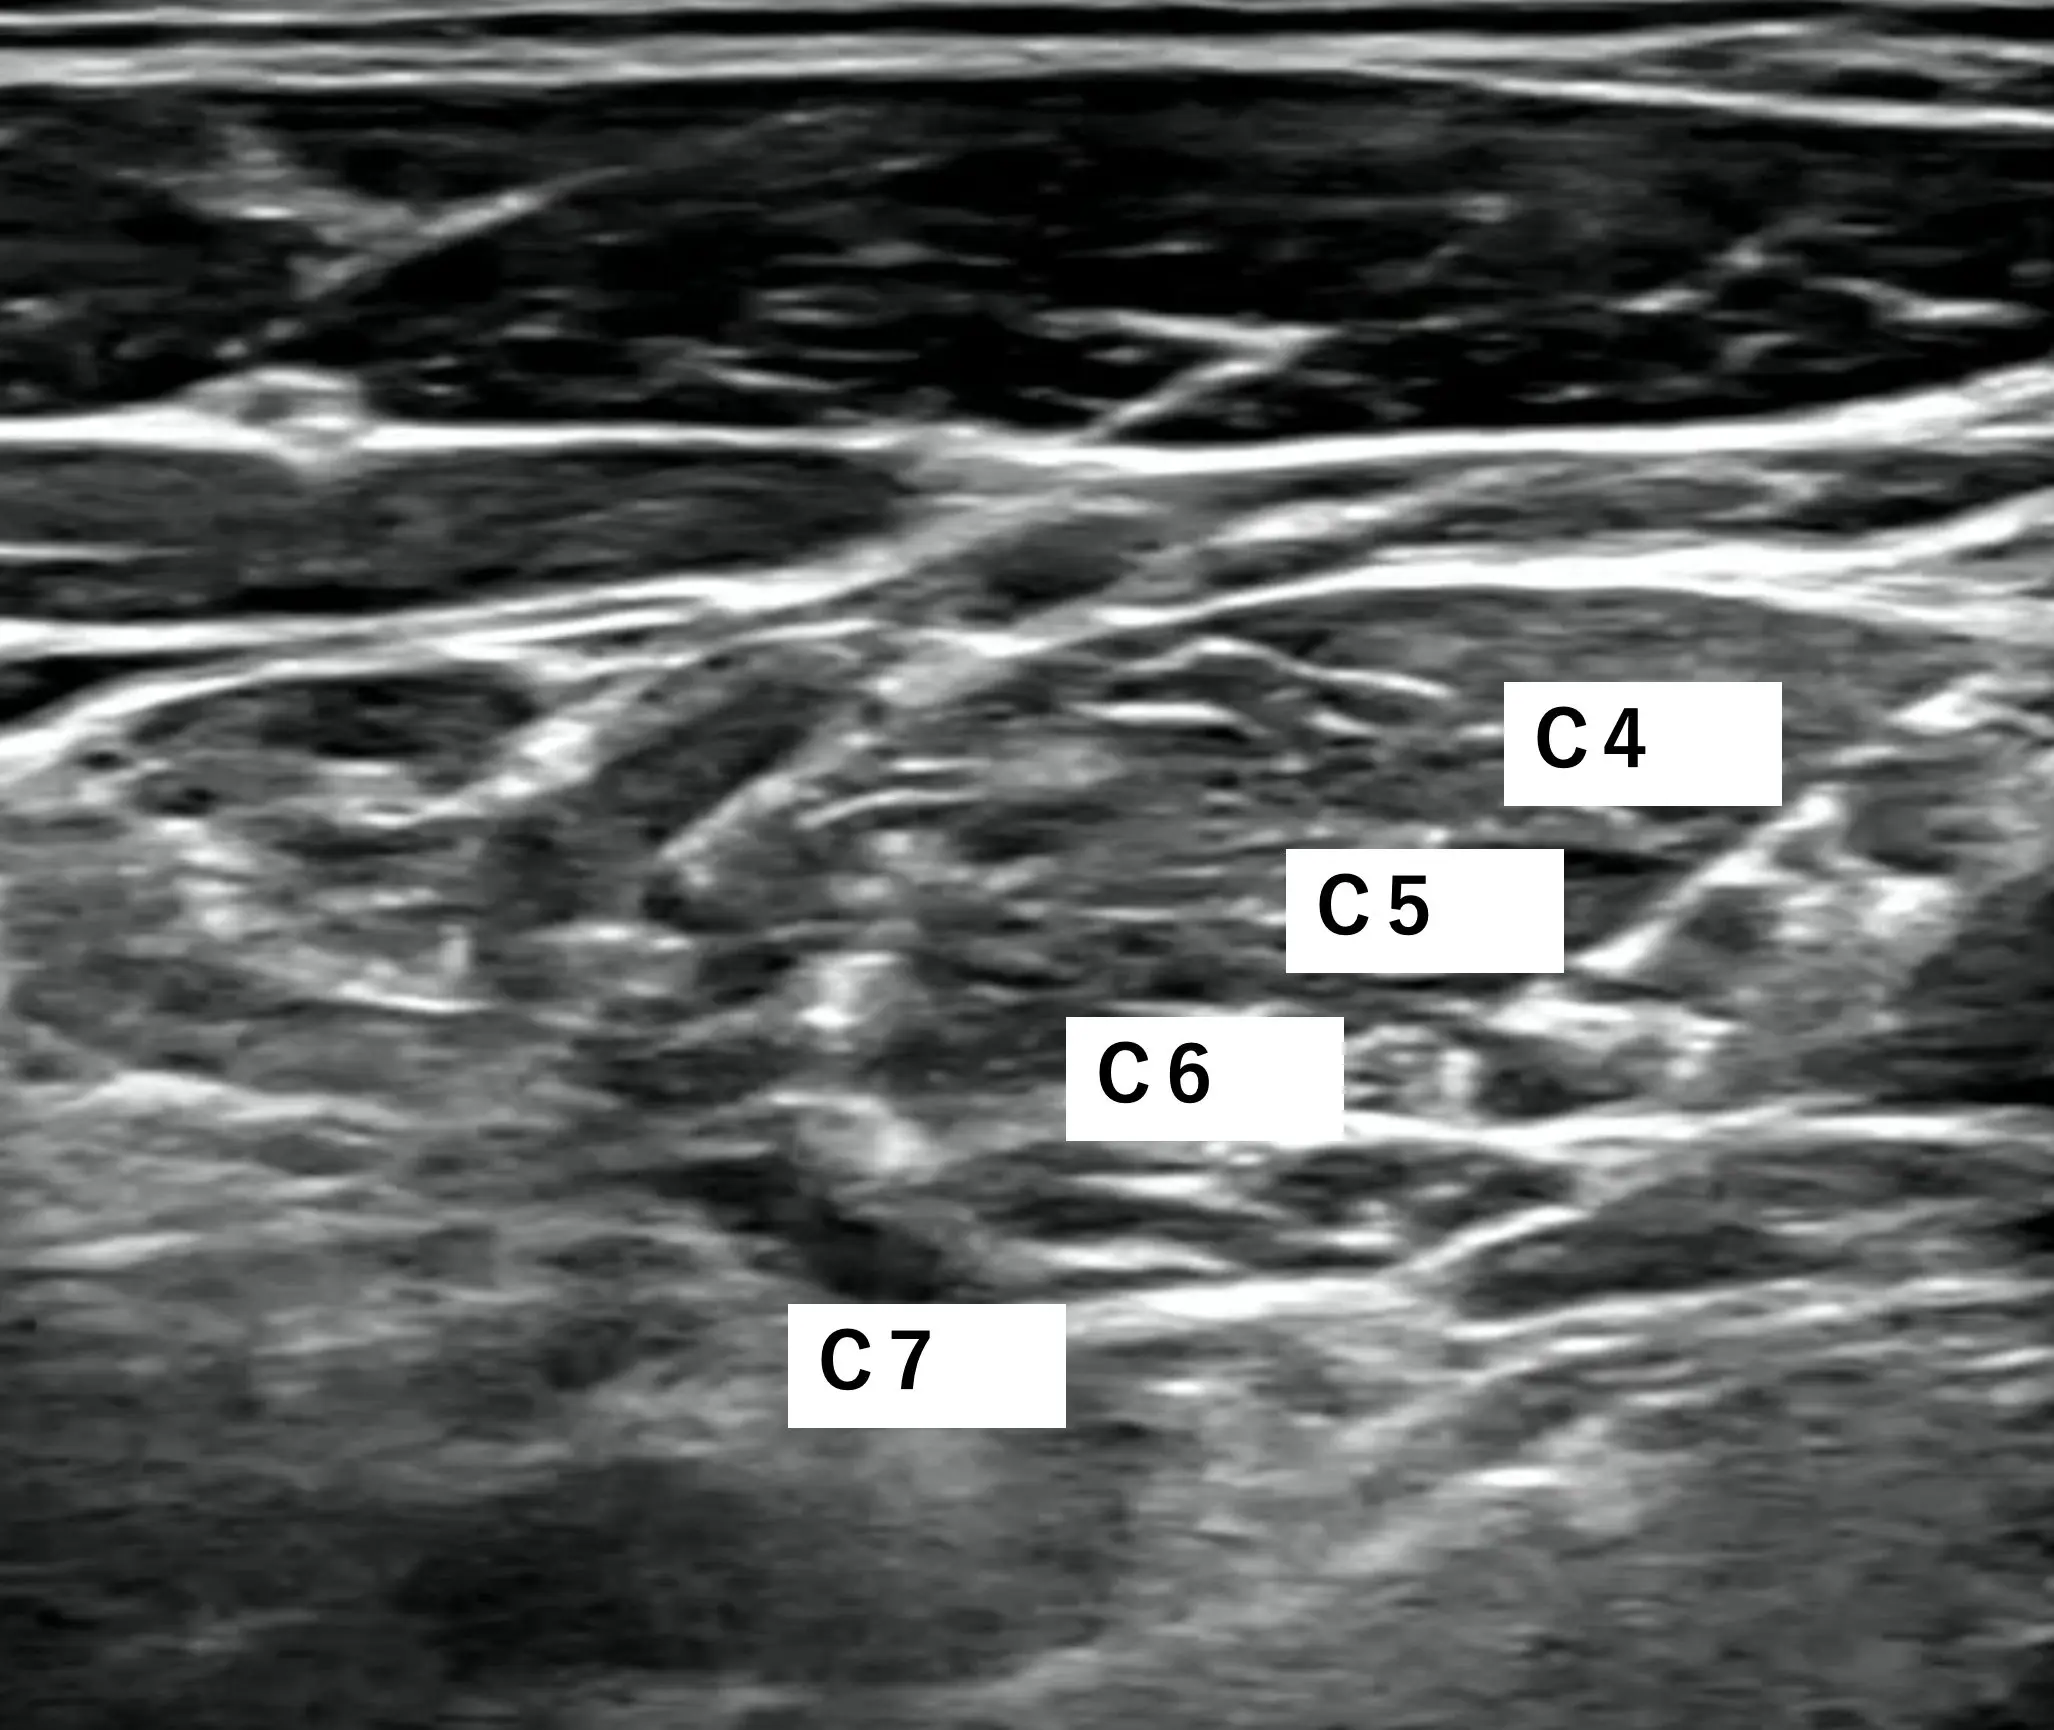

腕神経叢(brachial plexus)は、頸髄(C5~C8)と胸髄(T1)の神経根が合流して形成される神経の束で、肩から腕、手にかけての感覚と運動を司ります。

黒丸が神経です

これだけはっきり神経が見えるんです。なので安全に確実に手技が行えるというわけです!